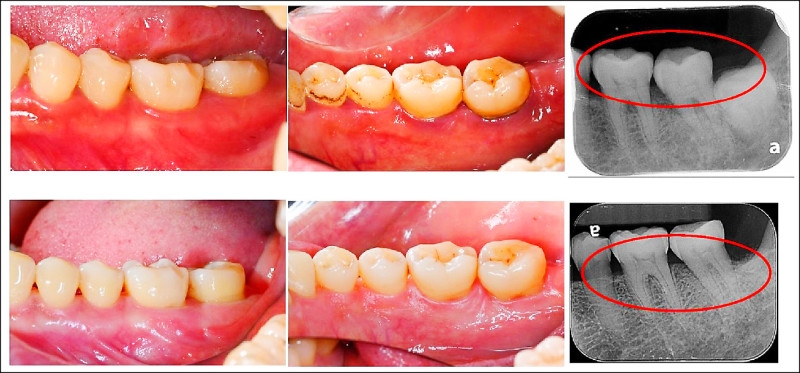

▲患者經過牙周治療後(下排為治療後),口腔清潔能力改善。